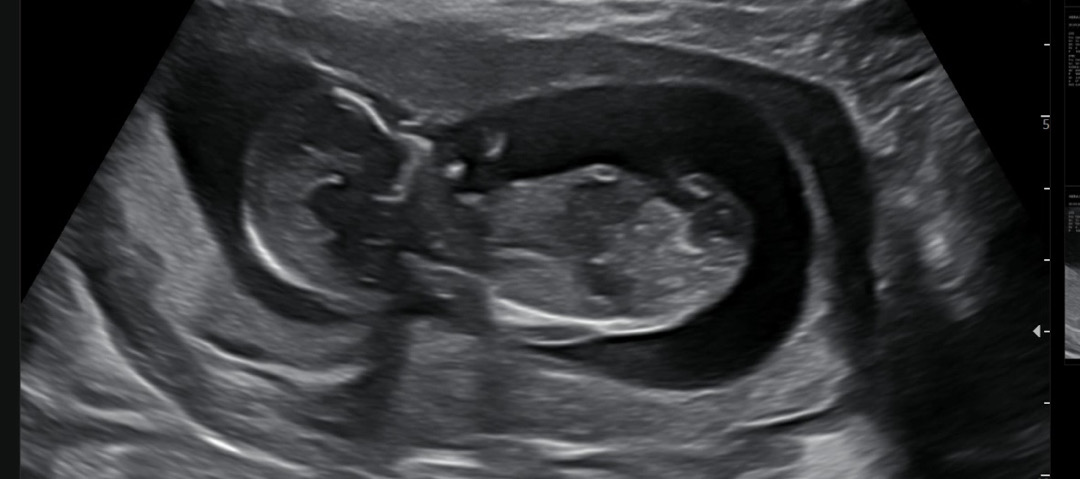

12주5일차 초음파 보고 왔어요 각도법 볼 수 있는 분 부탁드려요 🥹🥹

생식기가 안보이는 사진이네요!